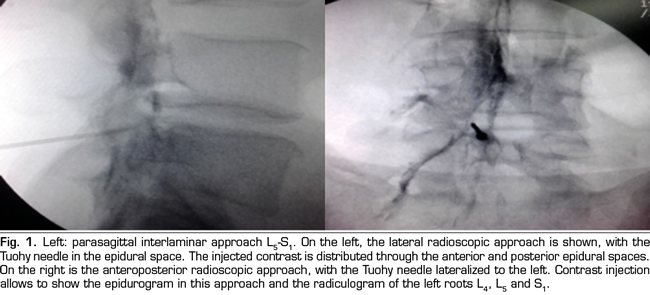

The procedure was performed in the surgical room. A peripheral venous catheter was placed with the patient on ventral decubitus position. Asepsis was conducted with alcoholic chlorhexidine and the local anesthesia was performed with 0.5 % lidocaine. Eighteen 3 1/2 or 4 3/4 inches tuohy needles (depending on patient size) were used for the parasagittal interlaminar technique. In the anteroposterior radioscopic view, the needle was inserted into the L4-5 or L5-S1 interlaminar spaces, using the tunnel vision technique, homolateral parasagittal of the side corresponding to the radicular pain (Figure 1). Loss of resistance was performed with saline. In the lateral view, a 4 mL contrast injection (Omnipaque©) was administered and the presence of anterior, posterior or both epidurograms was recorded (Figure 1). In the anteroposterior view the presence of radiculogram was recorded (Figure 1). A vial of betamethasone (12 mg of a mixture of phosphate and betamethasone acetate in 2 mL of solution) was then administered diluted with 3 mL of 0.5% lidocaine (total solution: 5 mL). The technical quality of the procedure was determined with the presence of paresthesia or concordant pain during the injection, and radiological data such as presence of radiculogram (Figure 1). Twenty two, 3 1/2 or 4 3/4 inches quincke needles were used in the transforaminal group and inserted using the oblique, lateral and anteroposterior radiological views.

The technical quality of the epidural steroid injection was evaluated in 21 out of 26 procedures performed with the parasagittal interlaminar approach. Anterior epidurograms, that is, achievement of the solution on the ventral epidural space, was obtained in 15 (71 %) of the patients (Figure 1 left); 17 (85 %) patients referred pain or paresthesia in the radicular territory during the injection, and a radiculogram was found in 12 (60 %) patients.